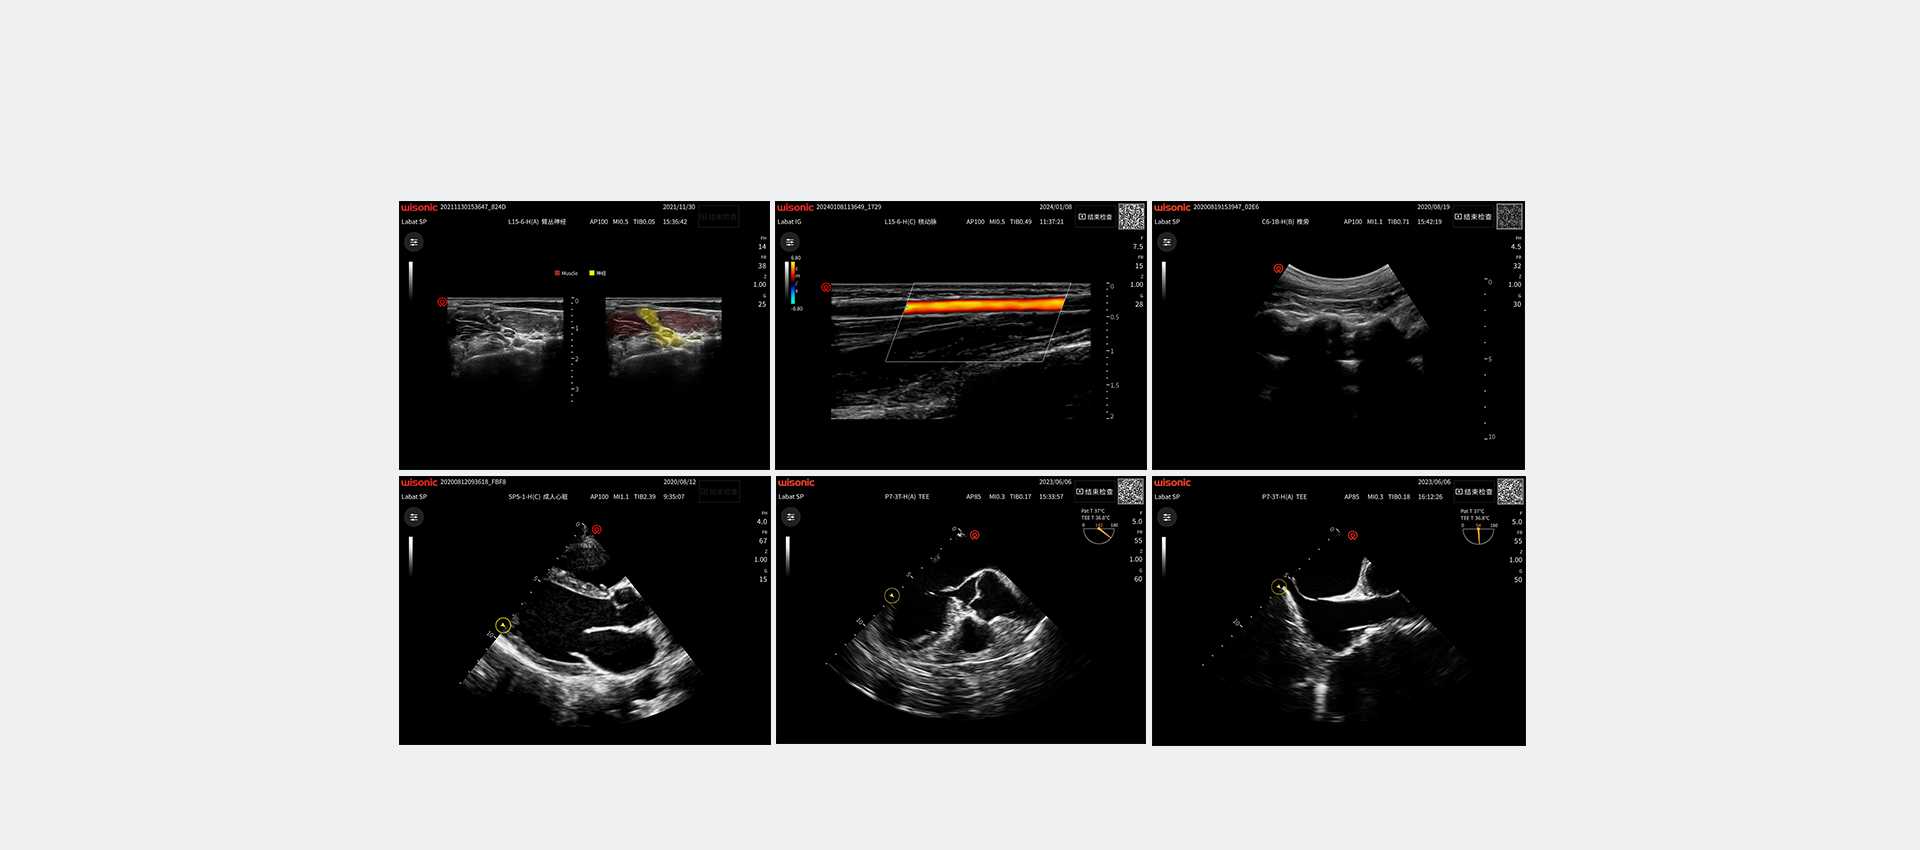

wiNerve

Intelligente AI-Nervenerkennung

Erkennung in Echtzeit

Cloud-L?sung

Unterstützung mehrerer Nerven

Excellent Clinical Images

Anwendungsbilder